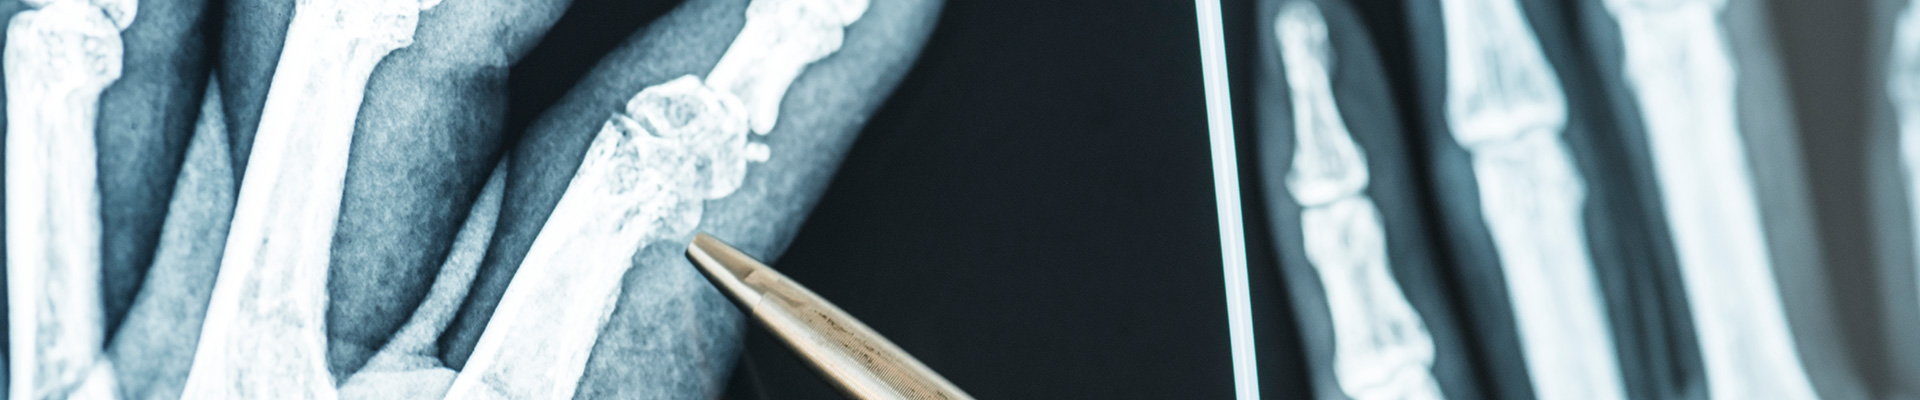

- Knochenverletzungen

- Rheumatische Erkrankungen (z.B. Arthritis, Arthrose, Fibromyalgie)